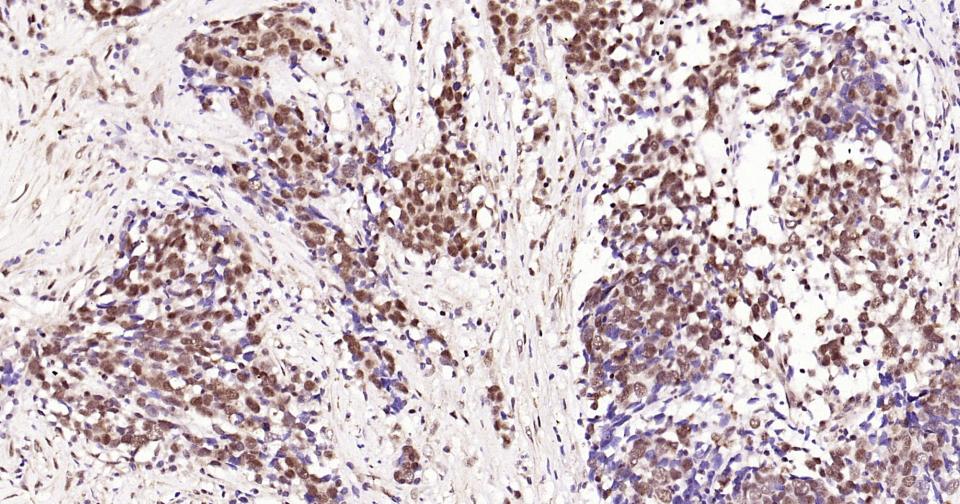

Paraformaldehyde-fixed, paraffin embedded Human Breast cancer; Antigen retrieval by boiling in sodium citrate buffer (pH6.0) for 15 min; Antibody incubation with Phospho-CREB-1 (Ser133) Monoclonal Antibody, Unconjugated(bsm-61105R) at 1:200 overnight at 4°C, followed by conjugation to the bs-0295G-HRP and DAB (C-0010) staining and DAB (C-0010) staining.